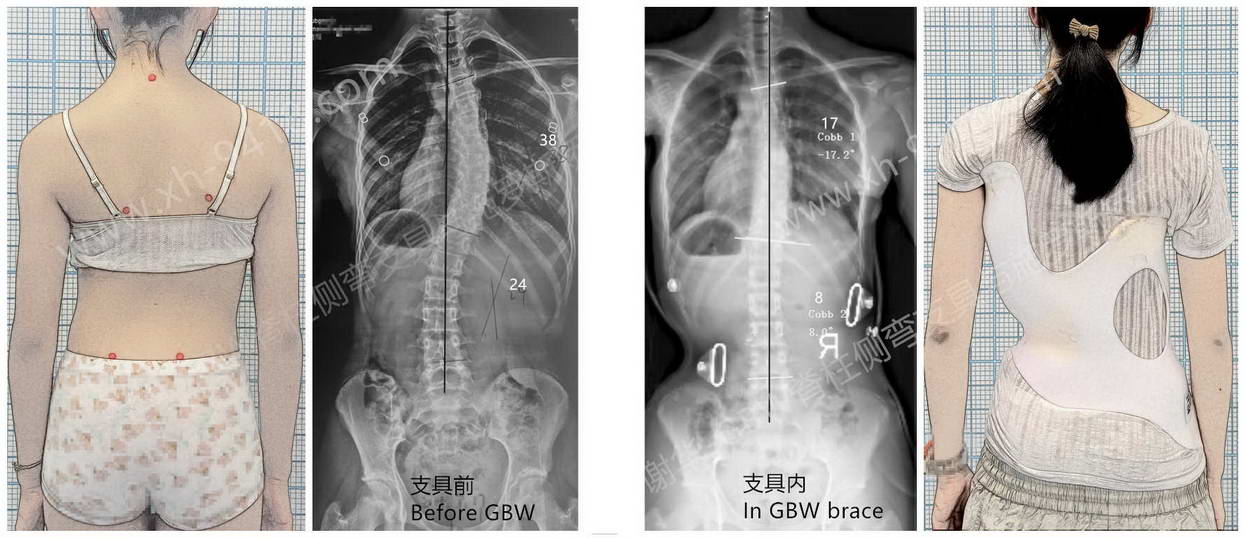

何同学,女,2011年出生,于2024年7月首次发现脊柱侧弯。8月来到成都工作室进行评估时,X片显示为“S”形双弯,但胸段偏离中线更明显,属于胸主弯型曲线。当时胸弯Cobb角为38°、腰弯24°,体表躯干旋转角(ATR)胸段15°、腰段2°。同时,骨龄评估提示 Risser 2级,意味着生长发育高峰即将结束,矫正时间窗口相对有限。

基于其曲线特点和旋转结构,选择了针对性较强的 GBW支具。佩戴后支具内X光显示矫正良好,胸段旋转及偏移得到有效控制。

经过一年左右的坚持配合,胸弯的度数明显下降,躯干外观也更加对称。体形变化尤为直观——肩胸平衡改善、背部隆起减轻,整体姿态更趋自然与协调。